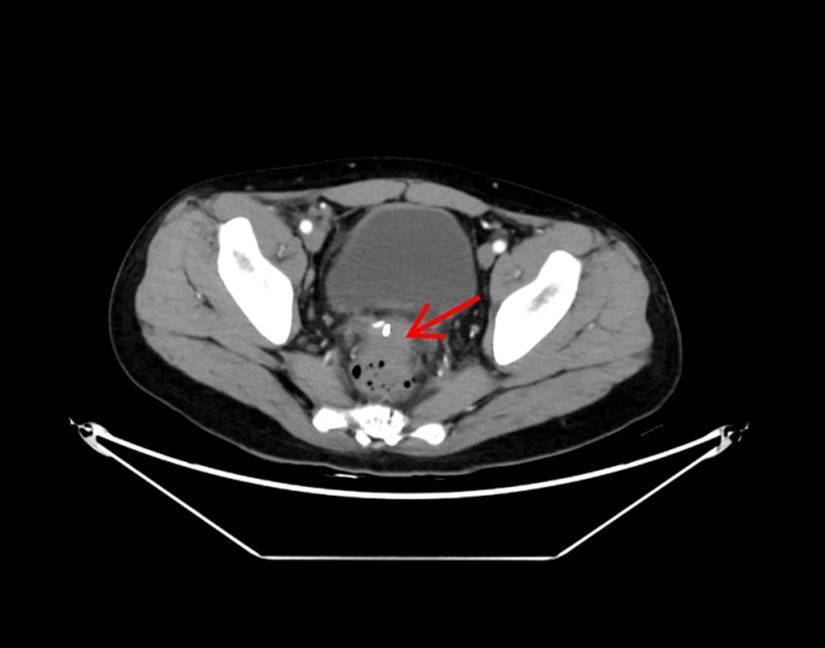

术前CT显示直肠前方一直径5cm圆形脓肿

术后4天复查CT显示脓肿基本消失

术后4小时,大量脓液即经肛门顺利排出,患者发热症状消退;术后2天,尿频、尿急、肛门下坠等不适症状完全缓解;术后4天复查CT显示,盆腔脓肿已基本消退;术后5天,患者顺利康复出院。出院前,患者含泪对医护团队表达感谢:“医者仁心,你们不仅治好了我身体的病痛,更治愈了我心底的恐慌,感谢青大附院的医护人员们。”